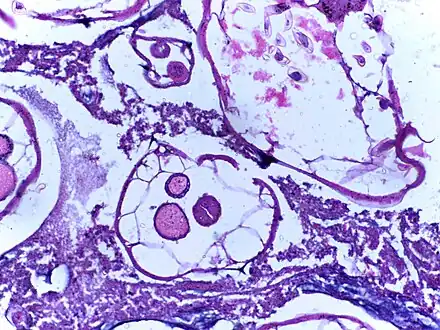

Identification and quantification of helminth eggs -

Micrograph of cut section of human appendix showing a pin worm.